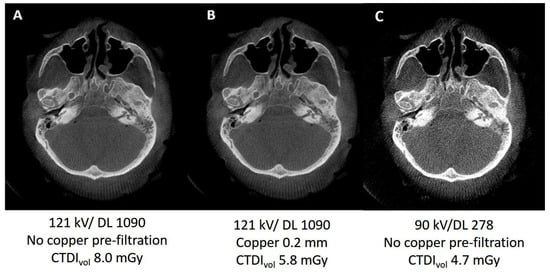

3.1.1. Variation of Tube Voltage